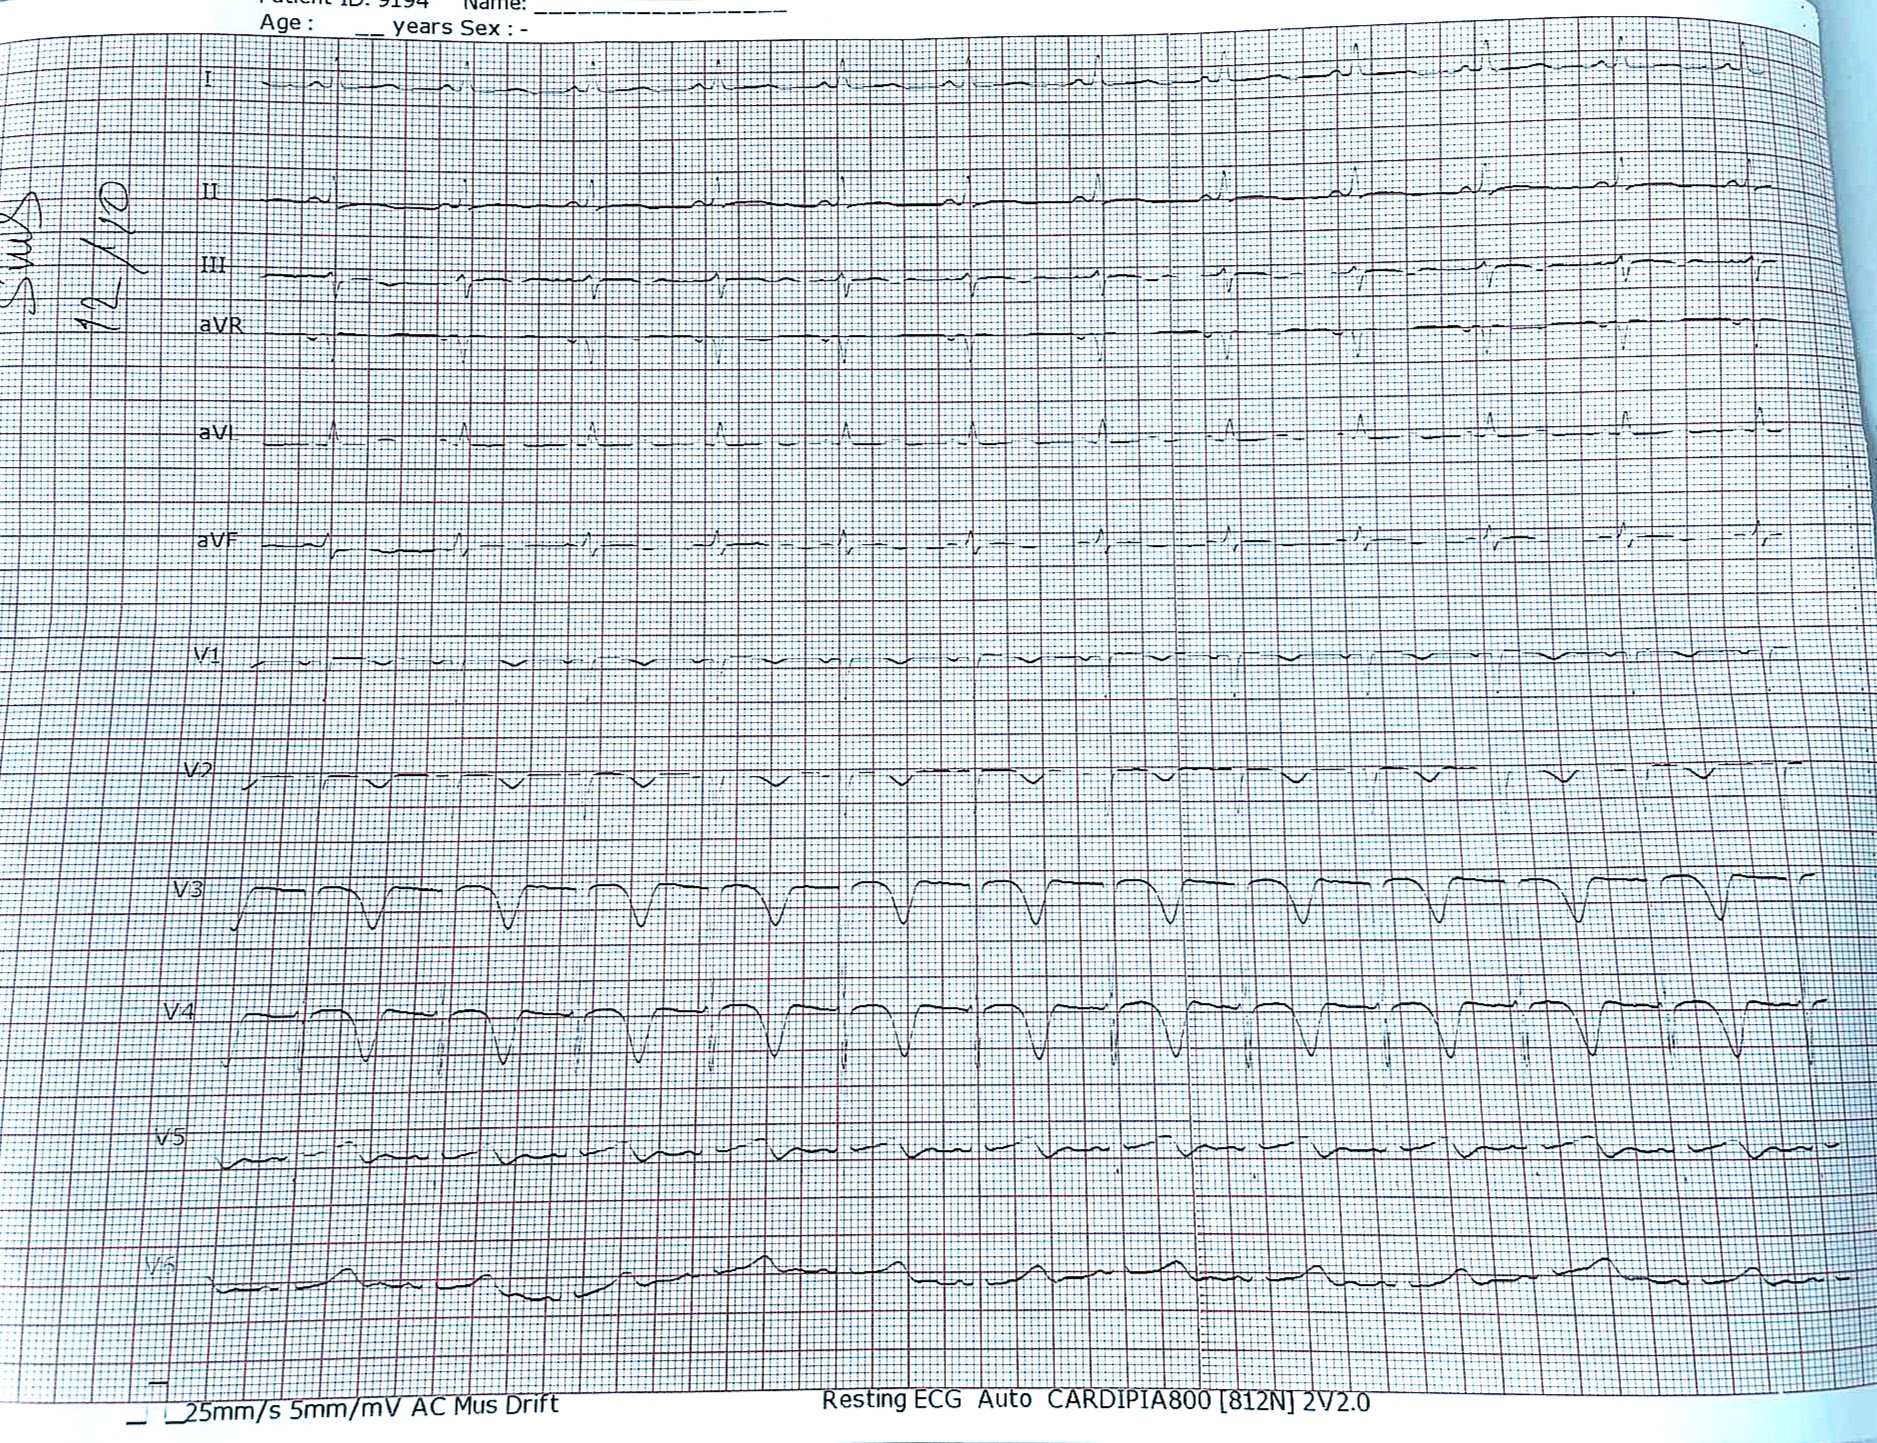

#ecg case sưu tầm: bệnh nhân nam 41 tuổi vào viện với lý do đau ngực, thất ngôn, yếu 1/2 người phải 2 ngày nay.

.

Nhận định cá nhân: Nhịp xoang. Tăng Áp lực nội sọ (QT dài + T âm khổng lồ). TD TMCT (R cắt cụt Trước ngực)